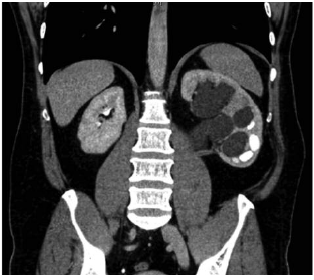

A 49-year-old white male, with long-standing pelviureteric junction obstruction

(PUJ), underwent a pyeloplasty in 1999. When the PUJ reoccurred, he underwent a

second procedure, which also eventually failed despite a metallic stent being

placed across the PUJ. This stent eventually calcified and became obstructed,

leaving him with a permanent nephrostomy tube (Figure 1). Renal autotransplant

was discussed, with potential of a Boari flap to save the organ and native

function. However the patient decided he wanted a nephrectomy due to

insurmountable pain despite optimal pain management and the indwelling

nephrostomy. Donor 1 received a full psychological assessment through an

external third party and was deemed to have capacity to proceed with

nephrectomy. The MAG3 renogram showed a 52:48 split function between kidneys.

Preoperative creatinine level was 86 IU/L, and estimated glomerular filtration

rate (eGFR) was 81 mL/min/1.73m2. An open elective nephrectomy was then

performed after again obtaining confirmation that the patient did not want to

have the organ autotransplanted. The patient was symptom free at 3 weeks

postsurgery, with no more pain and able to return to work. He maintained good

renal function and had no surgical complications. His 1-year eGFR postsurgery

was 70 mL/min/1.73 m2 with baseline creatinine of 95 IU/L, urea level of 7.8

mg/L, and hemoglobin level of 140 g/L.11

Figure 1. Pelviureteric Junction Obstruction in Donor 1